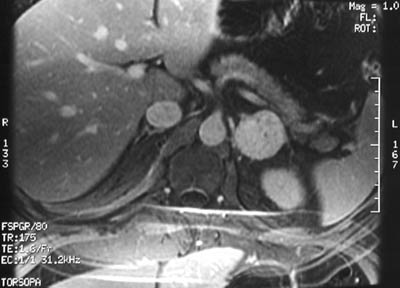

| The abdominal MRI scan seen here is a post Gadolinium T1 weighted image with fat saturation that demonstrates diffuse contrast enhancement in a pheochromocytoma of the left adrenal. This patient had a plasma norepinephrine level measured at 1200 pg/mL/H, which is very high. |